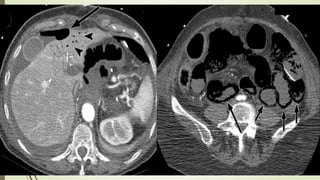

HERNIA DIRECTA

 Pasa anteromedial a vasos epigástricos inferiores

 Masa lateral a músculo recto

 «Signo lateral cresciente»

 CI desplazado y comprimido lateralmente, incluyendo grasa y demás

contenidos

HERNIA INDIRECTA

 Pasa superolateral a vaso epigástrico inferior  lateral y medial

siguiendo el CI

 Se muestra con el contenido habitual del CI, no se comprime ni

distorsiona